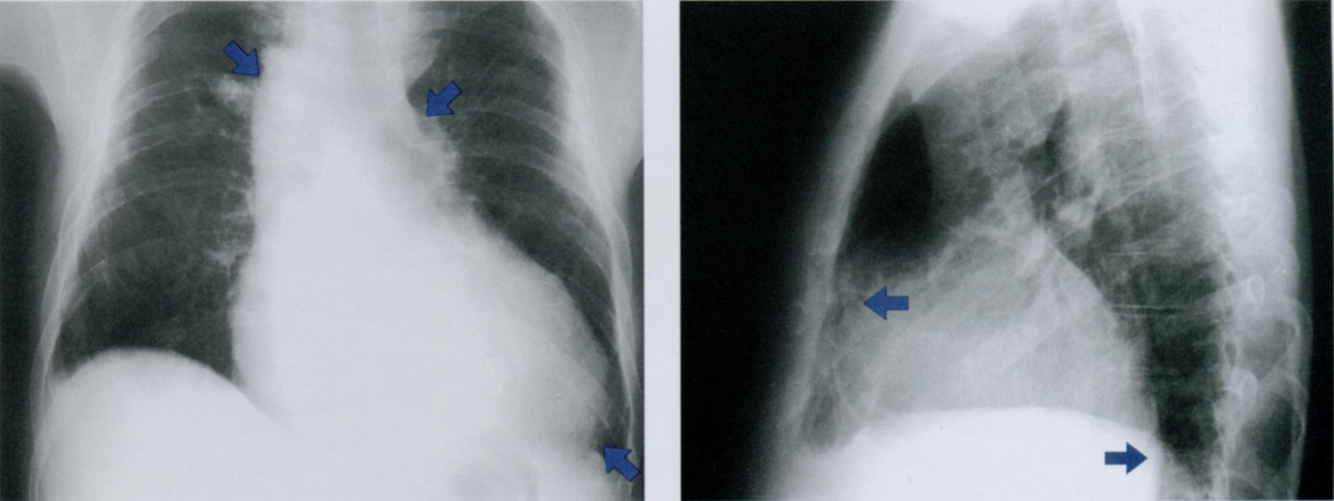

Оцените Rx снимки.

Назовите рентген-признаки митрального стеноза.

Стеноз митрального клапана нарушает опорожнение левого предсердия (ЛП),

а недостаочность приводит к рефлюксу крови в ЛП - это служит причиной его расширения.

В результате пороки митрального клапана приводят к формированию митральной конфигурации левого контура сердца на рентгенограмме грудной клетки (первый снимок).

Дилатация левого предсердия приводит к расширению талии сердца (косая стрелка) и может вызывать симптом двойного контура (синяя область втором рисунке).

Дилатация левого предсердия может быть настолько выражена, что его тень достигает правого контура средостения (горизонтальная стрелка на втором рисунке).

Расширение предсердия может увеличивать угол бифуркации трахеи (косые стрелки смотрят вверх) между правым (14) и левым (14b) главными бронхами (третий и четвертый снимки), подобно увеличенным подкаринным ЛУ или массивному перикардиальному выпоту.